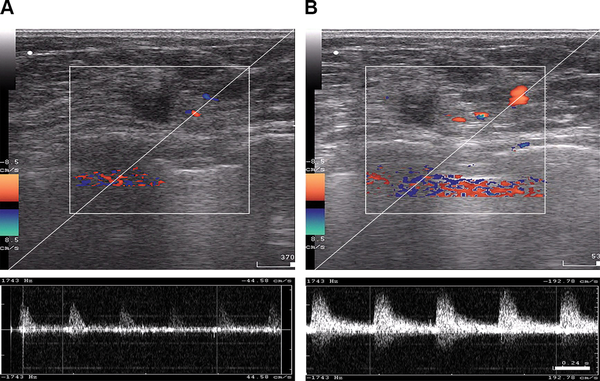

Figure 5

B-mode and color Doppler ultrasound imaging of tumor blood flow acquired from a patient with locally advanced breast cancer before regional inductive moderate hyperthermia (A) and 30 minutes after (B) treatment.

Color Doppler US examinations were recorded to assess blood flow in the breasts in the experimental group (Figure 5). RIMH significantly increased the number of color signals detected through the blood vessels in the breast tissue. The blood flow rate increased from 44.58 cm/s to 192.78 cm/s after treatment. The mean values for systolic blood flow were 3.5 times as high as those prior to the RIMH session. Similarly, the mean diastolic blood flow tended to raise after RIMH. Doppler signals from tumor vasculature were more variable due to spatio-temporal heterogeneity of breast tumors.